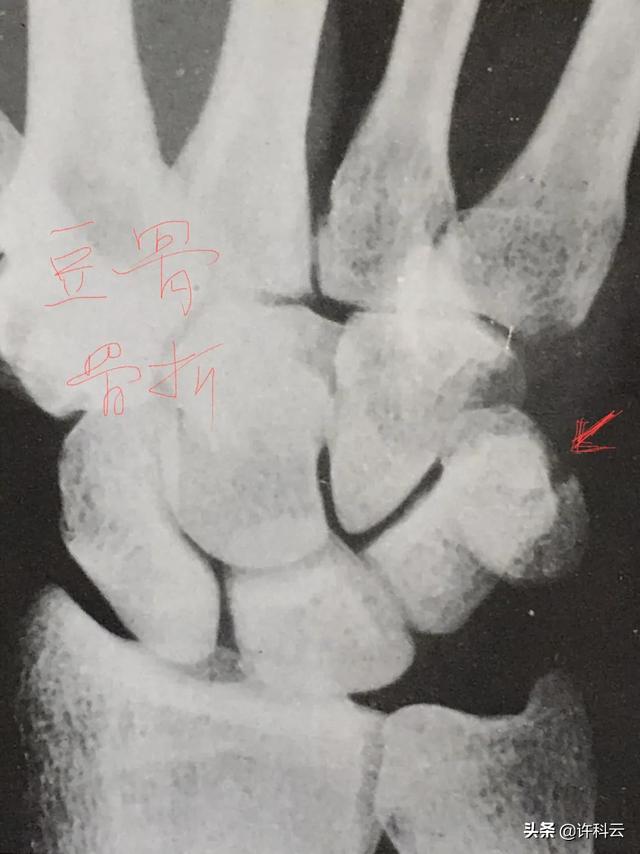

️如果5分钟就肿了怎么拍片还正常?因为腕部有八块不规则的腕骨,右手掌对人,从拇指侧顺时针数起:舟骨、月骨、三角骨、豆状骨、大多角骨、小多角骨、头状骨、钩状骨、只要临床症状上确认有骨折,就要从几个角度分别拍X光片,而且诊断腕骨骨折,既要有投照经验还要有看片经验,不规则的腕骨骨裂或骨折在影像重叠时无法看出骨折。

️你跌伤后已近一月,如果腕关节还肿,是骨折造成的,它有一个压痛点对应在某个腕骨上,如果没有骨折便为整个腕部肿胀及功能障碍、如果怀疑有骨折可再去拍片复查能看出。